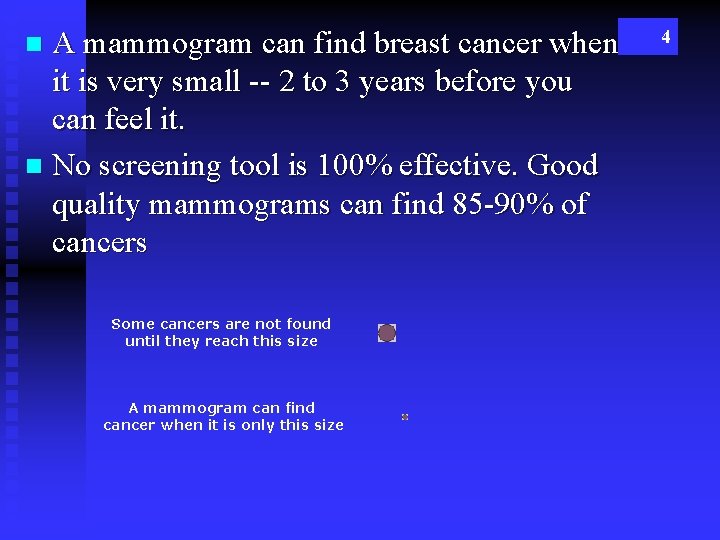

A mammogram can find breast cancer when it is very small -- 2 to 3 years before you can feel it. n No screening tool is 100% effective. Good quality mammograms can find 85 -90% of cancers n Some cancers are not found until they reach this size A mammogram can find cancer when it is only this size 4